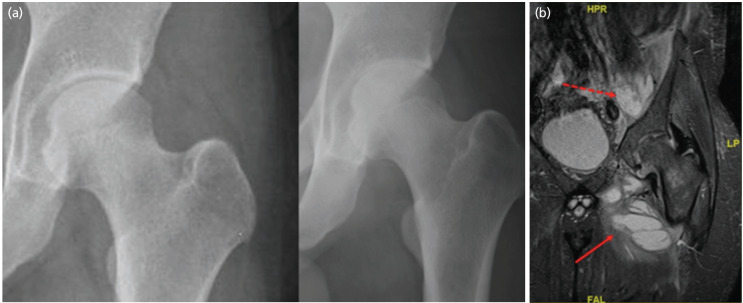

A 31-year-old man presented with abscesses of the left iliacus muscle, adductor muscles and left hip septic arthritis. Following surgical debridement and antibiotics, he remained infection free at 3 years. We present the radiographic evolution of the changes in his left hip . Despite destruction of the hip during initial follow-up, there was remoulding of the proximal femur with changes of avascular necrosis over a 3-year period with good hip function. Hip septic arthritis may result alarming radiographic changes during initial follow-up. Some patients may continue to improve clinically and radiographically in the short term.